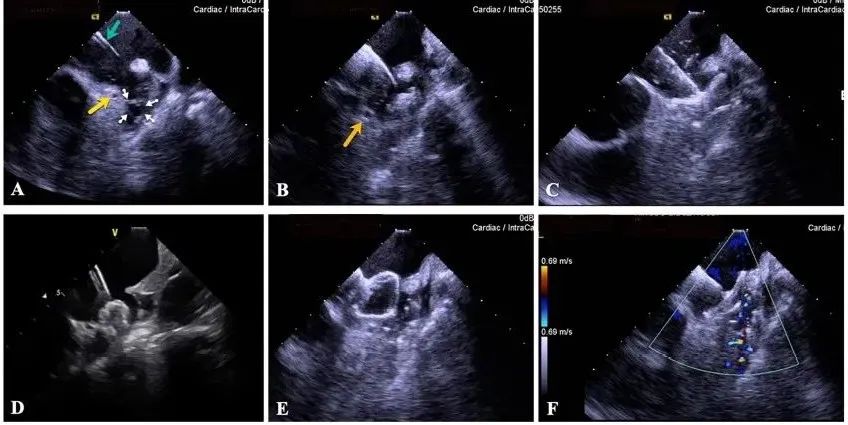

一種與心導(dǎo)管檢查相結(jié)合的超聲心動(dòng)圖診斷新興技術(shù),通過(guò)將超聲探頭置于心腔內(nèi)部,發(fā)射并接收超聲信號(hào),來(lái)精確獲取心臟解剖結(jié)構(gòu)、心臟血流動(dòng)力學(xué)等信息的實(shí)時(shí)成像。與其他影像技術(shù)相比,ICE技術(shù)具有操作簡(jiǎn)單、無(wú)輻射、安全性高、手術(shù)效率高、實(shí)用等優(yōu)勢(shì),ICE在很大程度上有望取代經(jīng)食道超聲心動(dòng)圖(TEE),成為電生理和結(jié)構(gòu)性心臟病領(lǐng)域的理想成像方式。

目前ICE技術(shù)已被應(yīng)用于左心耳封堵、房顫射頻消融、二尖瓣成形、房間隔缺損封堵等多種心臟介入手術(shù),應(yīng)用場(chǎng)景主要圍繞心臟電生理、結(jié)構(gòu)性心臟病等領(lǐng)域,目前以電生理應(yīng)用為主。數(shù)據(jù)顯示,我國(guó)結(jié)構(gòu)性心臟病介入器械市場(chǎng)規(guī)模已從2017年的4億元增長(zhǎng)至2021年的20億元,年復(fù)合增長(zhǎng)率達(dá)48.3%;預(yù)計(jì)到2025年,該市場(chǎng)規(guī)模將達(dá)到104億元,可以預(yù)見(jiàn)ICE市場(chǎng)規(guī)模也將同步高速增長(zhǎng),未來(lái)市場(chǎng)發(fā)展空間廣闊。

心腔內(nèi)超聲(ICE)技術(shù)壁壘極高,國(guó)內(nèi)主要廠商核心部件仍舊為進(jìn)口,集成了超聲和圖像處理最前端技術(shù),包括超聲探頭、線(xiàn)纜、軟件成像算法等,是當(dāng)前內(nèi)窺超聲方向最具挑戰(zhàn)的領(lǐng)域。ICE的應(yīng)用經(jīng)歷了2D平面成像、3D三維立體成像、以及4D的實(shí)時(shí)三維立體成像階段。